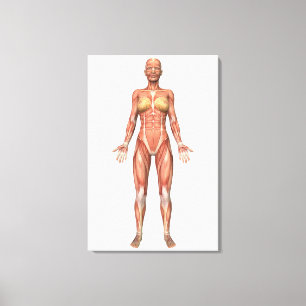

Poster Sistema Muscular Feminino, Vista frontal

Preço116,00 €